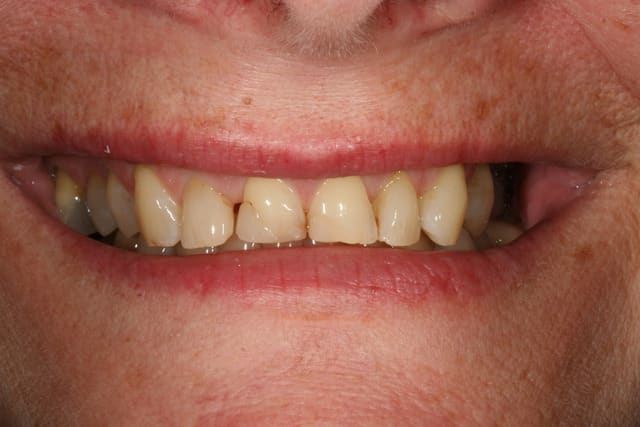

voilà le resultat collé

je suis resté trop supragingival, mais la patiente est très contente (ouf, c'est l'essentiel !)

elle a sa gouttière pour la nuit